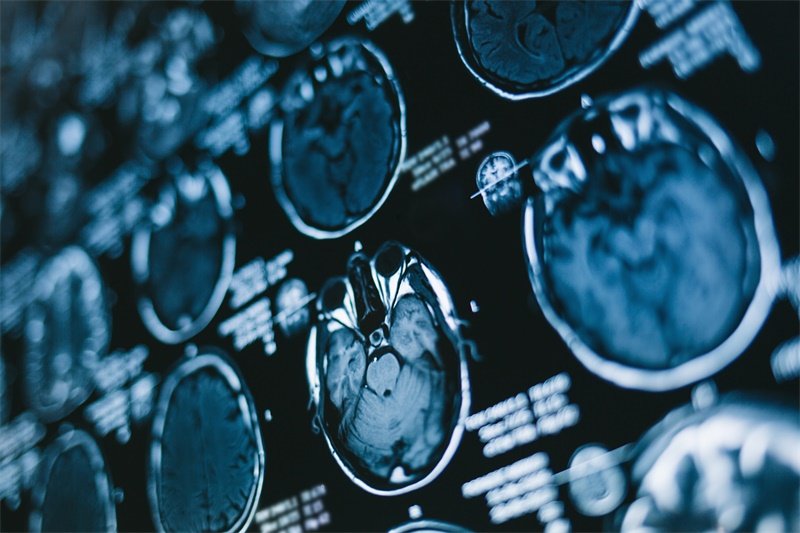

由于骶骨的解剖特点,肿瘤的早期症状可能不明显,这导致很多患者在确诊时已处于较晚期。因此,了解骶骨脊索瘤的相关知识,特别是影像学表现,是非常重要的。MRI作为一种无创的影像学检查手段,能够详细展示骶骨及其周围软组织的情况,对早期诊断和治疗方案的制定具有重要意义。

MRI能够提供高分辨率的图像,使得医生能够更加清晰地观察到骶骨及周围组织的结构变化。骶骨脊索瘤在影像学上的表现通常包括肿瘤的大小、形状及其对周围结构的侵袭程度等。这些信息对于制定治疗方案非常关键。

例如,MRI能显示肿瘤是否侵犯邻近的神经、血管及其他组织,帮助医生评估手术的可行性。

骶骨脊索瘤通常表现出特定的软组织信号特征,MRI可以很清晰地分辨肿瘤的性质和成分。例如,肿瘤的水肿、出血或钙化等特征,这些都能在MRI上清楚显示,帮助医生进一步分析病情。

骶骨脊索瘤的信号特征在不同序列的MRI上表现出差异。在T1加权成像上,肿瘤可能呈低信号,而在T2加权成像上则可能呈高信号。了解信号强度特征有助于医生进行准确判断。